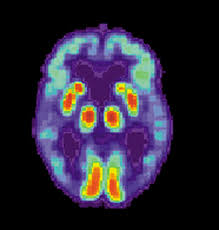

La OMS define la enfermedad de Alzheimer como una dolencia degenerativa cerebral primaria, de etiología desconocida, que presenta síntomas neuropatológicos y neuroquímicos característicos. El trastorno se inicia, generalmente, de forma insidiosa y lenta y evoluciona progresivamente durante un período de años.

La enfermedad de Alzheimer o demencia tipo Alzheimer, es un trastorno encefálico de deterioro crónico y progresivo que se acompaña de efectos profundos en la capacidad de recordar, aprender y razonar. Produce un gran deterioro en la persona.